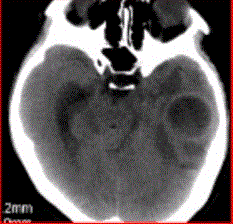

问题 患者女,26岁,头痛、低热10d余,既往有左侧慢性中耳炎病史。CT表现如下图。 有关脑脓肿的DWI表现,正确的是

选项 A.DWI上脓肿腔均呈高信号,ADC呈低信号 B.经过治疗的脓肿腔DWI也可呈等信号或低信号 C.DWI脓肿周围水肿高信号,ADC高信号 D.DWI上脓肿腔低信号,ADC高信号 E.脓肿壁DWI高信号

答案 B